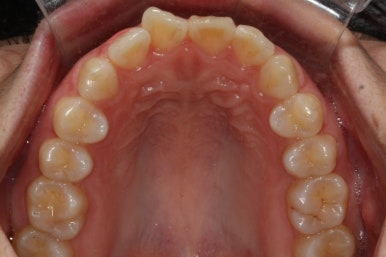

부산앞니교정 키다리아저씨치과에 처음 내원하셔쓸 당시의 입안 모습입니다.

앞니가 살짝 삐뚤어진 것을 볼 수 있고, 삐뚤어진 사이에서 약간의 틈새도 있었습니다.

예전에 치료 받으셨던 앞니 부분에 약간의 변색도 와서 미적으로 좋지 못한 상황이였습니다.